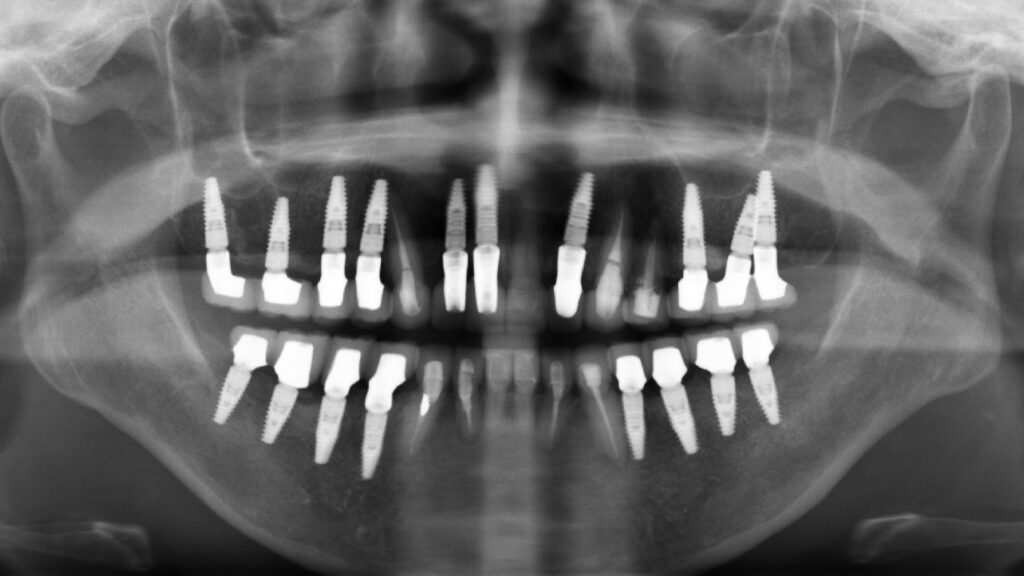

| 治療方法 | インプラント治療・根管治療 |

| 抜歯部位 | FDI表記 11.13.14.22.24.25.35.44.45 |

| 治療期間 | 8ヶ月 |

| 治療費 | 50万円/1本 |